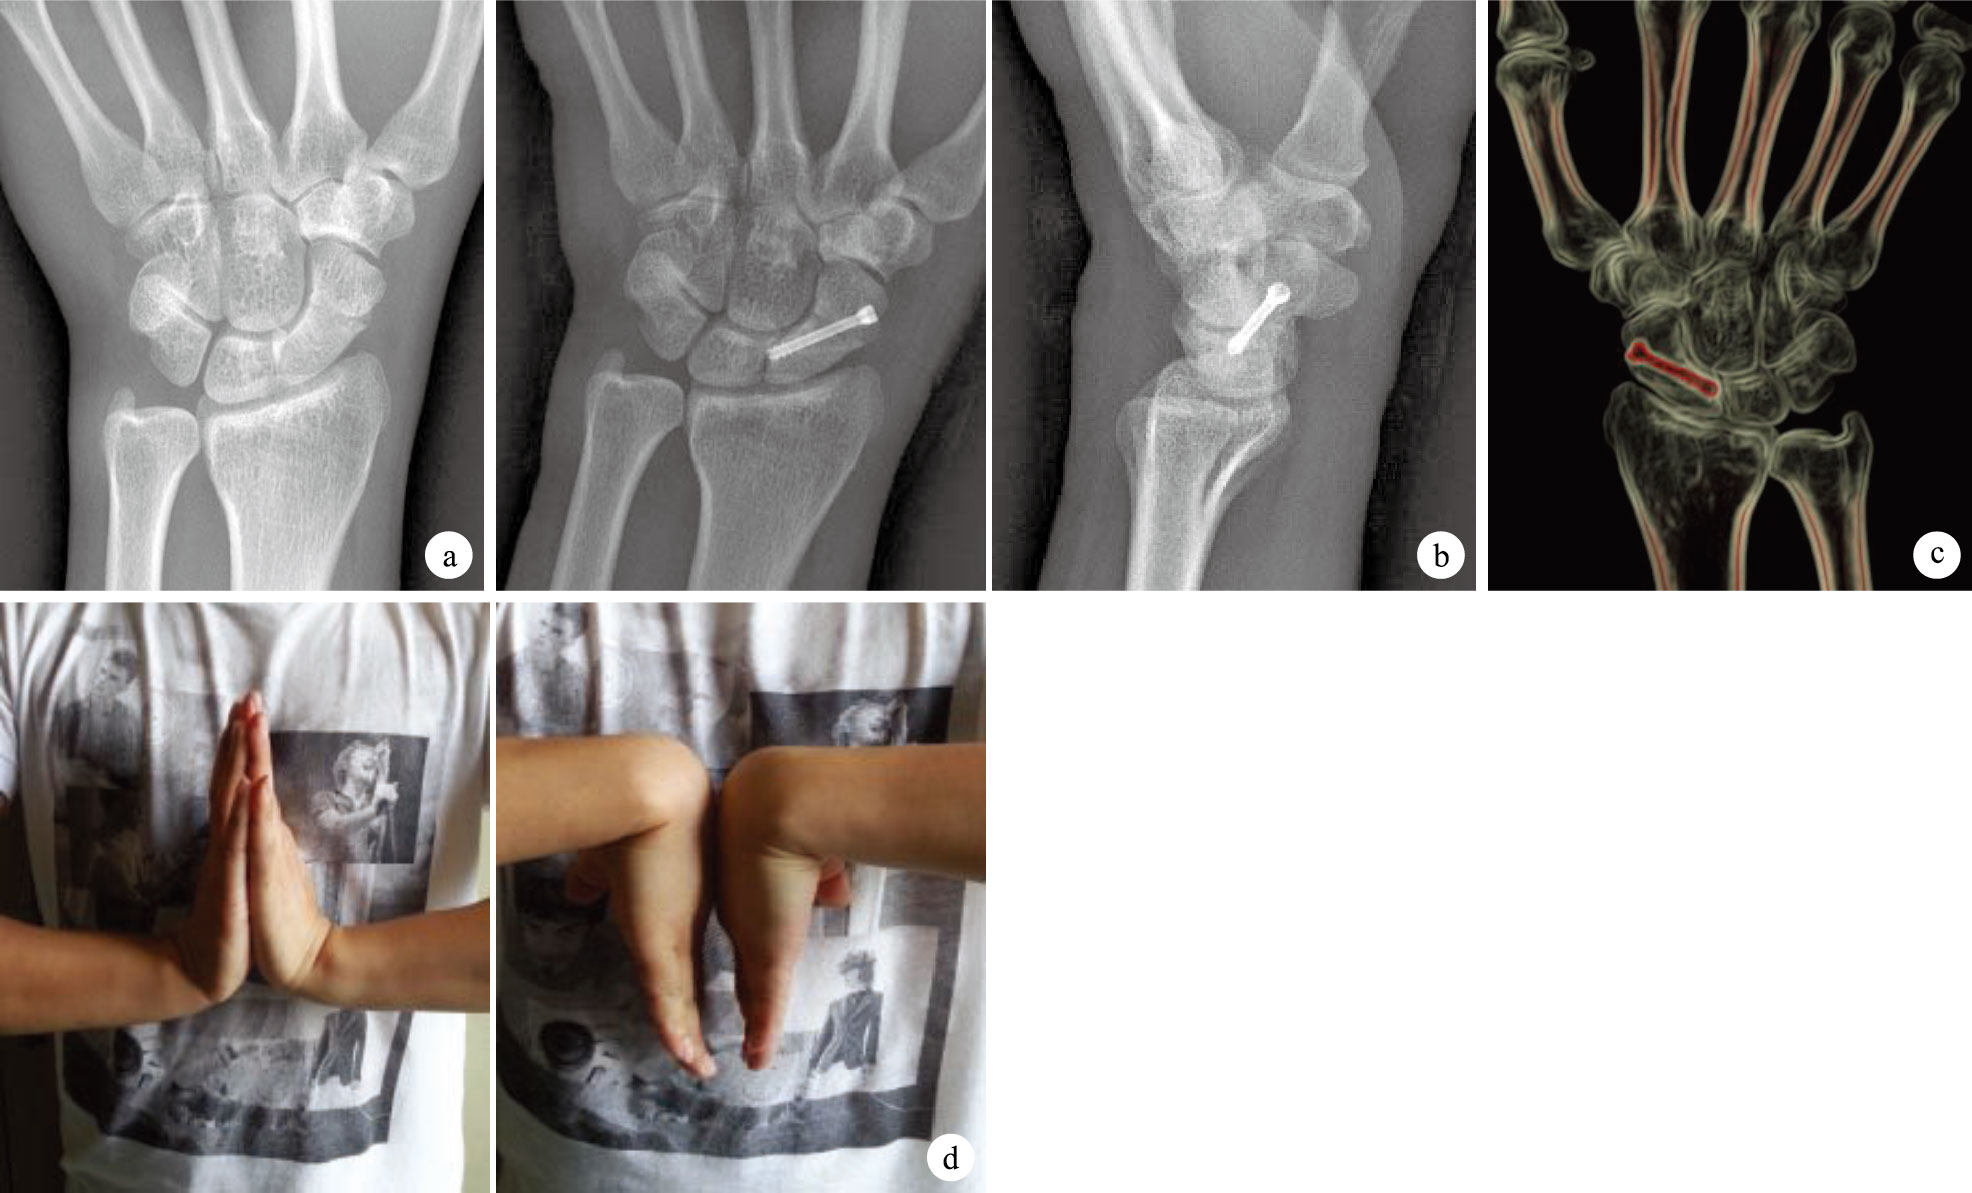

末次隨訪時,微創組腕關節活動度為(104.40±3.46)°,顯著高于外固定組(94.20±2.42)°及切開復位組(96.40±2.66)°,比較差異有統計學意義(P<0.05);切開復位組及外固定組比較,差異亦有統計學意義(P<0.05)。腕關節Mayo功能評分,外固定組獲優6例、良5例、中2例、差3例,優良率為69%;切開復位組獲優9例、良7例、中2例、差2例,優良率為80%;微創組獲優16例、良3例、中1例,優良率為95%。3組優良率比較差異有統計學意義(P<0.05)。見圖 6。

② 內固定方法:臂叢神經阻滯麻醉下,前臂旋后并以可透X線支具將腕關節固定于背伸30°、尺偏15°位(佩戴與術前CT掃描時同一支具、同一位置),在支具邊緣固定導板,在導板引導下經皮自舟骨結節鉆入0.8 mm導針。C臂X線機透視導針方向,若有偏差,則以此導針方向為參考,重新鉆入導針調整至合適方向,測量螺釘長度,擰入Herbert螺釘,透視內固定位置滿意后拔除導針,切口縫合1針,見圖 5。術后處理同切開復位組。